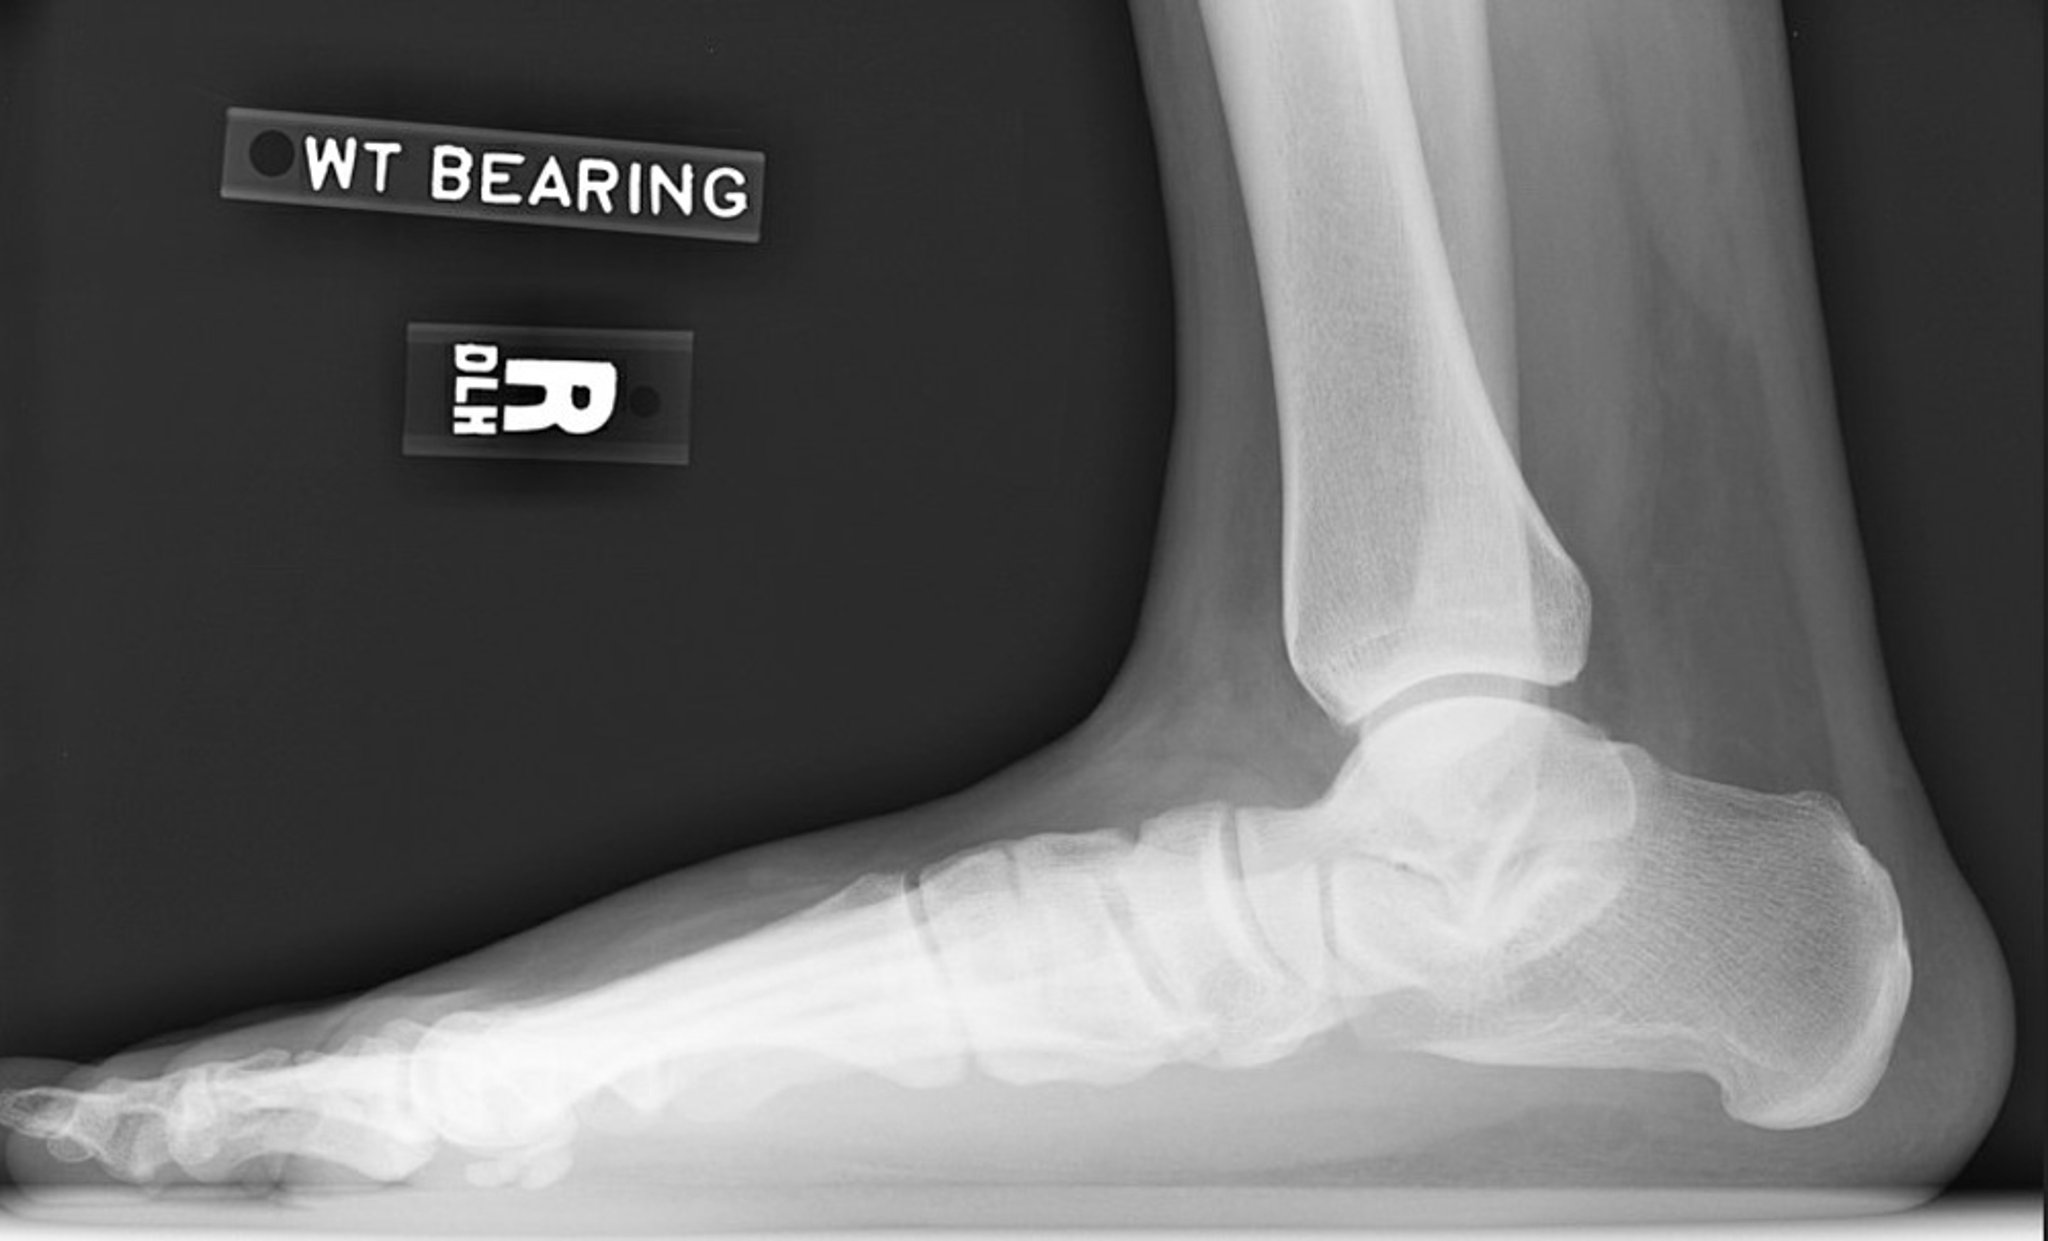

Рентгенограмма при плоскостопии

Боковая рентгенограмма правой стопы: потеря высоты свода стопы. Обратите внимание на уменьшение угла наклона пяточной кости и угла отклонения таранной кости. Подтаранный сустав сужен, но голеностопный сустав относительно сохранен.

Image courtesy of James C. Connors, DPM.